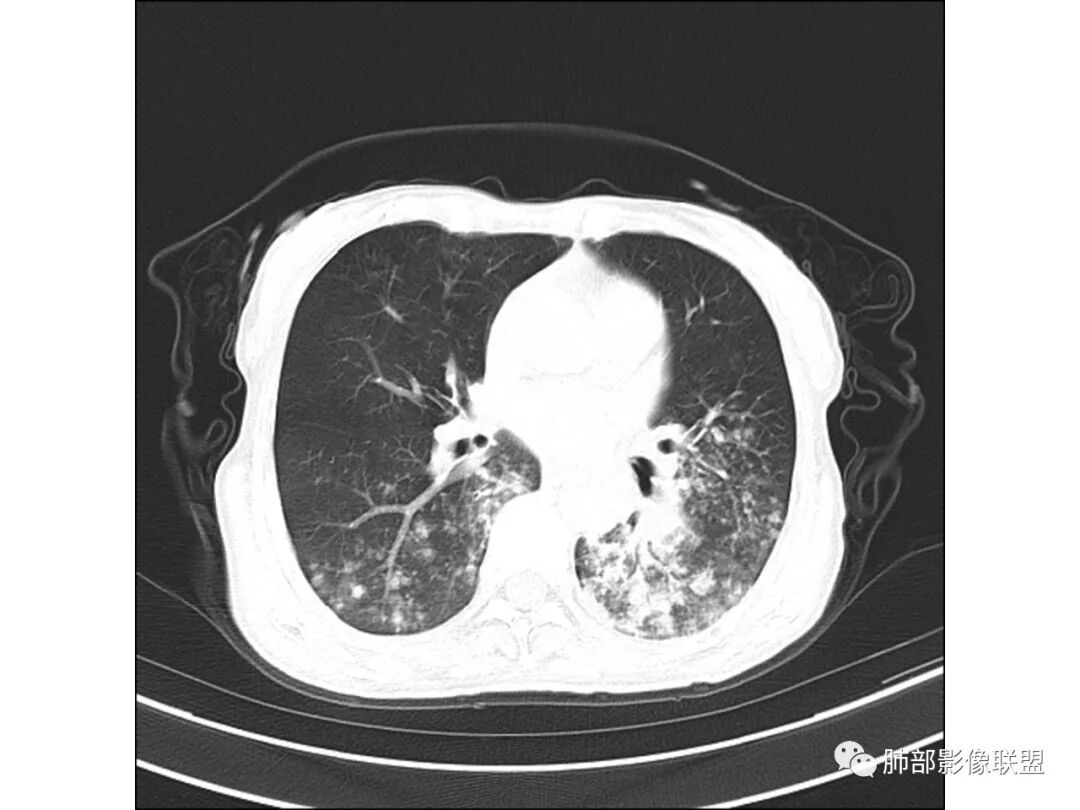

慢性迁延不愈患者 发热伴脓痰 双肺多发小结节伴磨玻璃影 左肺下叶体积缩小 支气管扩张伴实变 实变内支气管不规则 平扫密度尚均较肌肉稍低 支气管扩张感染基础上合并淋巴瘤待查 建议增强穿刺

老年女性,慢性病程,有反复咯血、发热,左下胸廓塌陷,双肺下叶多发片状实变影,伴多发结节,左下肺实变为主伴卫星灶,支气管扩张,伴虫噬样空洞及支气管壁钙化,首先考虑结核,鉴别粘液腺癌

老年丶反复发作2年,但双肺下叶多发腺泡结节,延气道分布,影像不符合陈旧病变,左下实变影,伴牵拉支扩,考虑慢性病变首先考虑吸入性肺炎,建议结合病史是否有隐性误吸,可查胃镜、气管镜丶钡透,除外食管、气管瘘。鉴别腺癌丶放线菌丶努卡菌丶NTM

患者老年女性,反复咳嗽 咳痰 活动后胸闷 气短,胸ct:病变以左肺下叶体积缩小,呈大片实变,实变组织内可见 左肺下叶支气管开口扩张,右肺下叶背段多发结节样病灶,周围有毛玻璃影。良性考虑感染性病变,ABPA ?结核?;恶性考虑:粘膜相关淋巴瘤。

双肺多叶段多发腺泡结节,延气道分布,双下肺为诸,左下肺大片实变影,伴牵拉支扩,老年人首先考虑支气管肺炎。鉴别腺癌。

双下肺多发腺泡结节,左肺下叶实变,彭隆,结核伴感染,鉴别结核伴粘液腺癌。

双肺下叶多发片,结节,左下肺实变,局部膨隆,粘液腺癌?鉴别结核。

晨读病例,老年女性,病程长,左侧胸廓缩小,双下肺叶多发片状实变影,伴多发结节及树芽征,左下肺实变,有坏死空洞,支气管扩张壁增厚有钙化,考虑结核,鉴别粘液腺癌,淋巴瘤,排除异物

病灶位于中下肺部,左下叶应该是源头,其余是播散灶

以双肺下叶背段及右肺上叶后段为主,是结核的好发部位

首先这幅图支气管很多地方是扭曲的,远端扩张的特别厉害。如果是肿瘤,首先考虑淋巴瘤,因为支气管可直达远端,稍扩张,但是它的前提是周围要实性占位的,而且它不会这样扭曲变形。我们看这个病例的支气管扩张,它支气管扩张占大部分区域,中间稍有些实性的结构,这就不符合了。这幅图你会发现所有支气管都是扩张的,实性部分偏少,外围胸水。所以我更倾向慢性炎性病变,能够引起支气管扩张的炎性病变有哪些?结核?NTM?支扩伴感染?大方向是慢性炎性病变。这些左下肺播散出来的病灶,咳中等量黄浓痰,我考虑还可能合并细菌感染。

1.双肺斑片影、大小不等结节影,边界不清,密度较均一,钙化不多见,可见树丫。

2.左肺下叶大范围病灶,其间柱状支气管扩张相当显眼。

这些都支持慢性炎性改变。

3.我们知道继发性肺结核为典型的慢性消耗性疾病,较少出现高热及较大量浓痰。该患者病灶密度较均一,新旧不等的特点并不突出,缺少高密度区,双肺上叶比较干净,夸张的支扩也有别于结核病灶导致的“鸡爪样”改变。

4.两次培养出鸟-胞内分枝杆菌,其为致病菌之一当无异议,是否有其他病原菌趁火打劫未能确定。

5.影像学改变可以用非结核分枝杆菌感染解释。